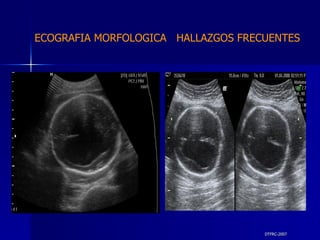

DTFRC-2007 ECOGRAFIA MORFOLOGICA  HALLAZGOS FRECUENTES   MATERIAL Y METODO ES UN ESTUDIO DESCRIPTIVO, RETROSPECTIVO  DE ESTUDIO ECOGRA FICOS REALIZADOS ENTRE MARZO 07 A MARZO 08 EQUIPO DE ALTA RESOLUCION   VOLUSON 730 PRO  MEDISON SA 8000 live MEDISON SA 8000SE CRITERIO DE INCLUSION:   POBLACION GENERAL    GESTACIONES  20 a 24 SEMANAS   UNIVERSO  N 211

DTFRC-2007 ECOGRAFIA MORFOLOGICA  HALLAZGOS FRECUENTES   Sistema Nervioso Central  8  Cardiovascular  0 Genitourinario  6 Musculos Esqueleticos  2 Gastrointestinales  2  Otros  12  Total  30   NUMEROS DE ANOMALIAS POR SISTEMA n N  211

DTFRC-2007 ECOGRAFIA MORFOLOGICA  HALLAZGOS FRECUENTES   GESTACIONES MULTIPLES  N 211 SINDROME TRANSFUCIONAL FETO FETAL (15/20 )